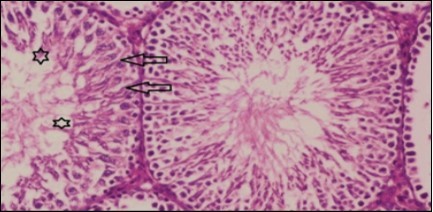

Testis Histopathological Observations

Histological examination of control rats' testis showed normal histological structure of the seminiferous tubules with an increase in the spermatogonia and other spermatocytes compared with the diabetic rats which showed an obvious decrease in the count of germinal cells generally and sloughing of germ cell in the lumen of seminiferous tubules in addition to absence of the mature sperms (Figure 3 and Figure 4). Rats tested of Fenugreek group and those treated with Glimepiride (Figure 5 and Figure 6) presented an increase in the number of spermatogenic cells and mature sperms with few focal necrotic cells. Whereas the combination therapy group showed normal histological structure of the seminiferous tubules with normal spermatogonia, presence of ledying cells and more mature of sperms (Figure 7). STZ reduced testosterone production, suggesting a decrease in the function of both Leydig (testosterone producing cell) and Sertoli (spermatogenesis) cells, which might be caused by a reduction in insulin secretion. These changes are probably due to increased Reactive Oxygen Species (ROS) production by accelerated Advanced Glycation End Products (AGE) formation 31 hexosamine and Protein Kinase C pathway. The administration of Fenugreek seeds to diabetic rats significantly decrease of sperm shape abnormality and improve the sperm count 32. Glimepiride reduced sperm abnormality and increased testis weights and sperm count by its antioxidant action 30. The potential protective efficacy of Fenugreek seed extract when added to Glimepiride was observed on reproductive systems.

Figure 4.Photomicrogragh of testis section of diabetic rat showing the sloughing of germ cells towards lumen of seminiferous tubules, absence of spermatozoa with low height of germinal epithelium and congested wide interstitial tissue (star). (H&E) (40x).

Photomicrogragh of testis section of diabetic rat showing the sloughing of germ cells towards lumen of seminiferous tubules, absence of spermatozoa with low height of germinal epithelium and congested wide interstitial tissue (star). (H&E) (40x).